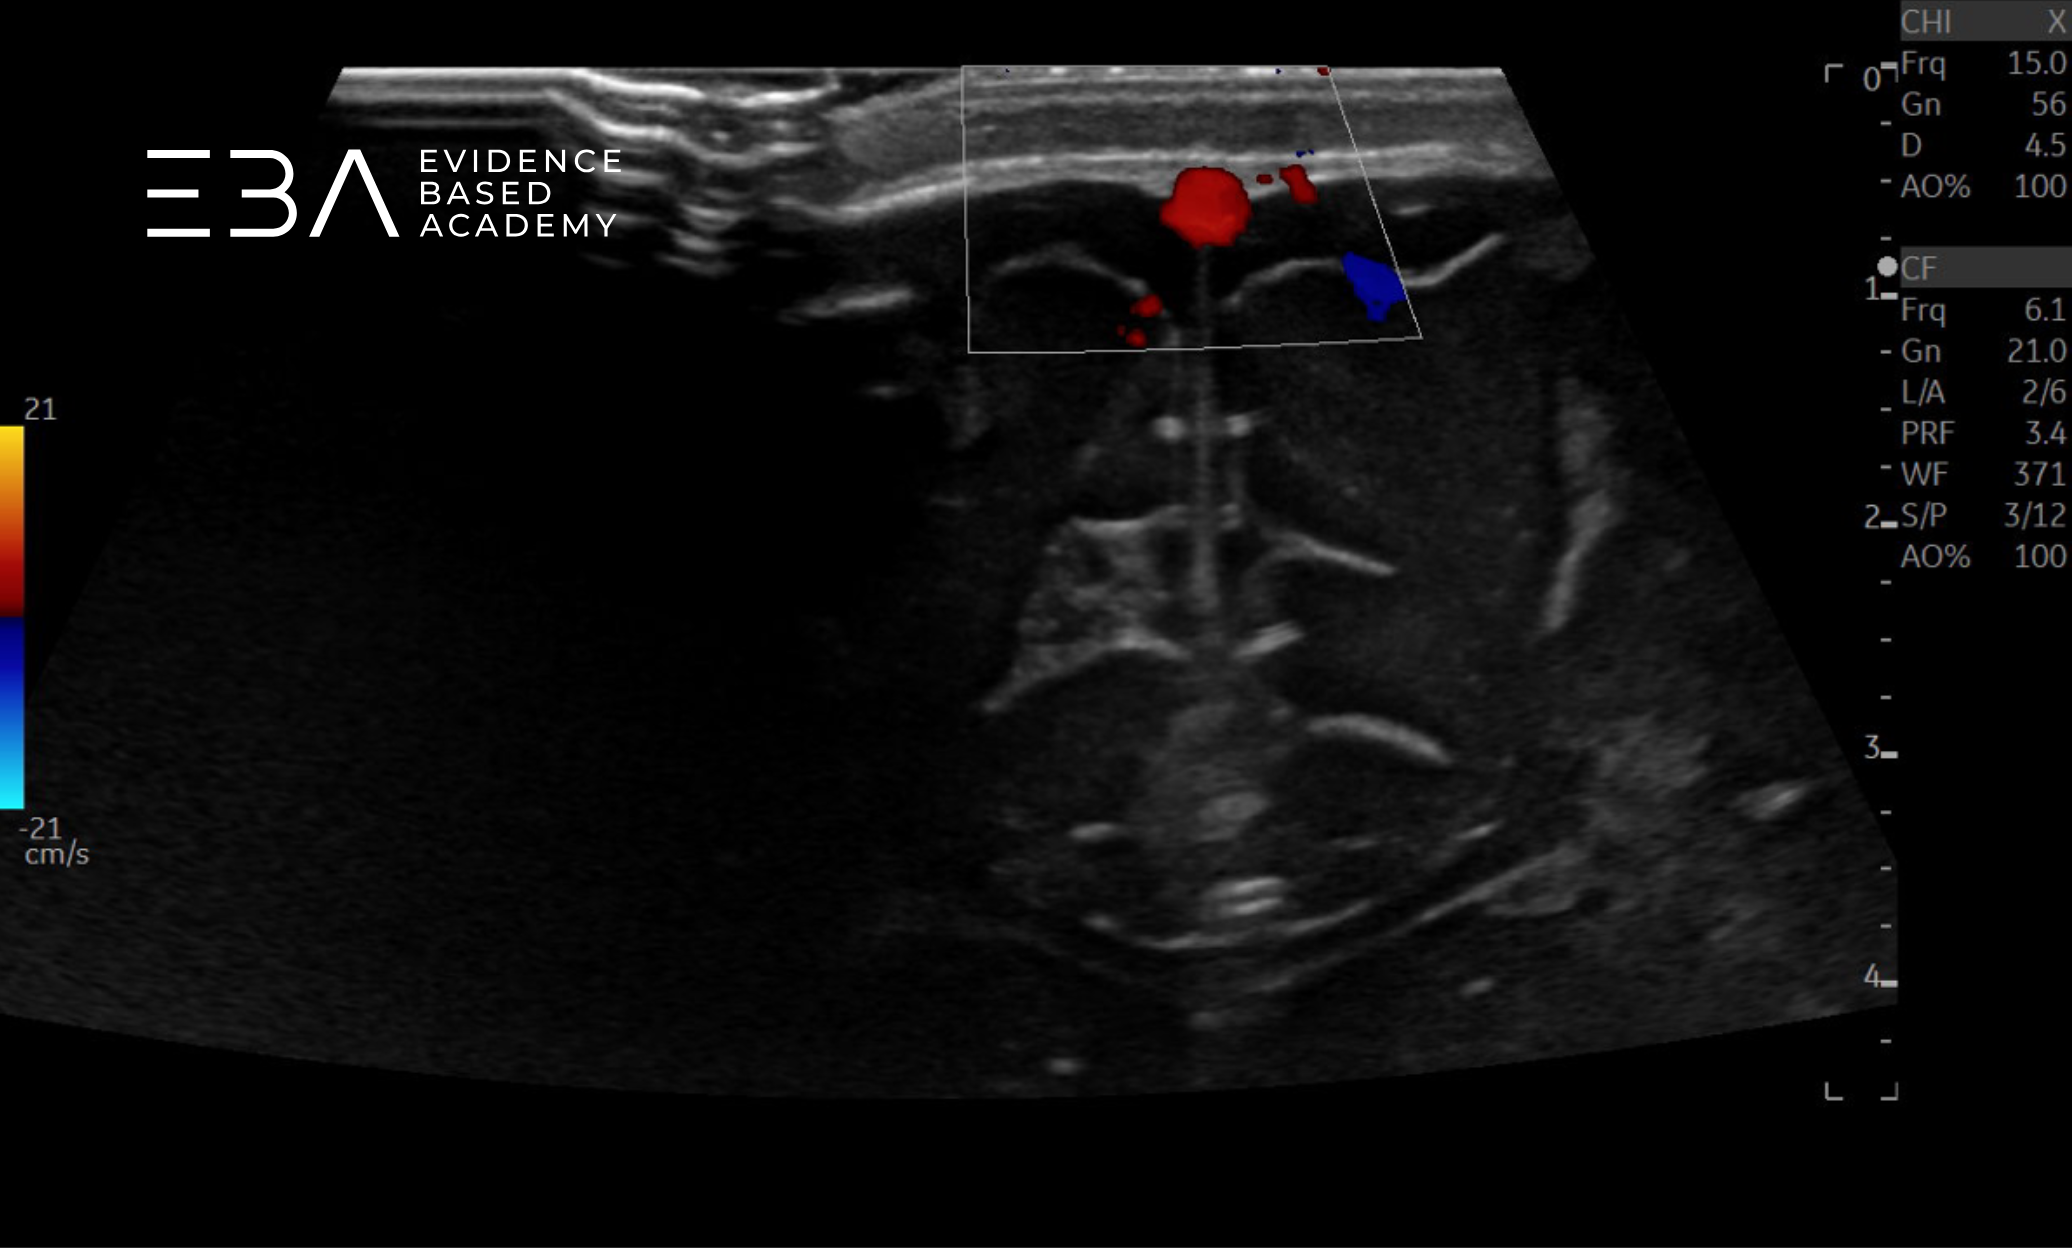

Badanie dopplerowskie

Badanie metodą Dopplera kolorowegopulsacyjnego umożliwia ocenę drożności naczyń wewnątrzczaszkowych oraz zmian hemodynamicznych mózgu noworodka (1, 2). Współczesne aparaty umożliwiają wizualizację przepływów rzędu 2 cm/s, co pozwala na uwidocznienie drobnych naczyń, takich jak naczynia pnia mózgu, żyły podwyściółkowe uchodzące do żył wzgórzowo-prążkowiowych oraz tętnice perforujące (3).

Obrazy koła Willisa w opcji Color Doppler uzyskujemy rutynowo w projekcji czołowej przez ciemiączko przednie lub w projekcji osiowej przez okno skroniowe. Wybór dostępu zależy od naczynia, które chcemy ocenić, lub od wygody badającego. Do rutynowego badania przesiewowego ciemiączko przednie jest zwykle wystarczające, natomiast do szczegółowej oceny koła Willisa lepszy jest dostęp przezskroniowy (6).

zdj. b

Głowica liniowa. Widoczny przepływ przez zatokę strzałkową górną.

Kluczowym kryterium różnicującym BESS od poszerzenia przestrzeni podtwardówkowej jest obecność żył korowych widocznych jako hiperechogeniczne struktury linijne w przestrzeni podpajęczynówkowej – w poszerzeniu przestrzeni podtwardówkowej naczynia te nie są widoczne w przestrzeni przymózgowej. W razie wątpliwości opcja Color Doppler pozwala na potwierdzenie obecności żył korowych w przestrzeni podpajęczynówkowej.